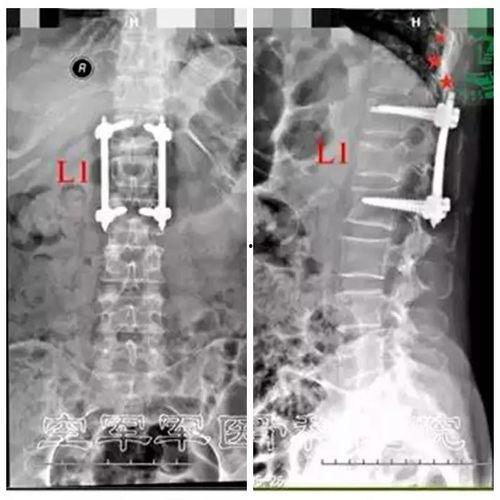

1. 腰椎的结构:通过视频,我们可以清晰地看到腰椎的骨骼、肌肉和神经分布。了解这些结构,有助于我们更好地保护腰椎。

2. 腰椎常见问题:腰椎疼痛、坐骨神经痛、腰椎间盘突出等都是常见的腰椎问题。视频会详细讲解这些问题产生的原因和症状。